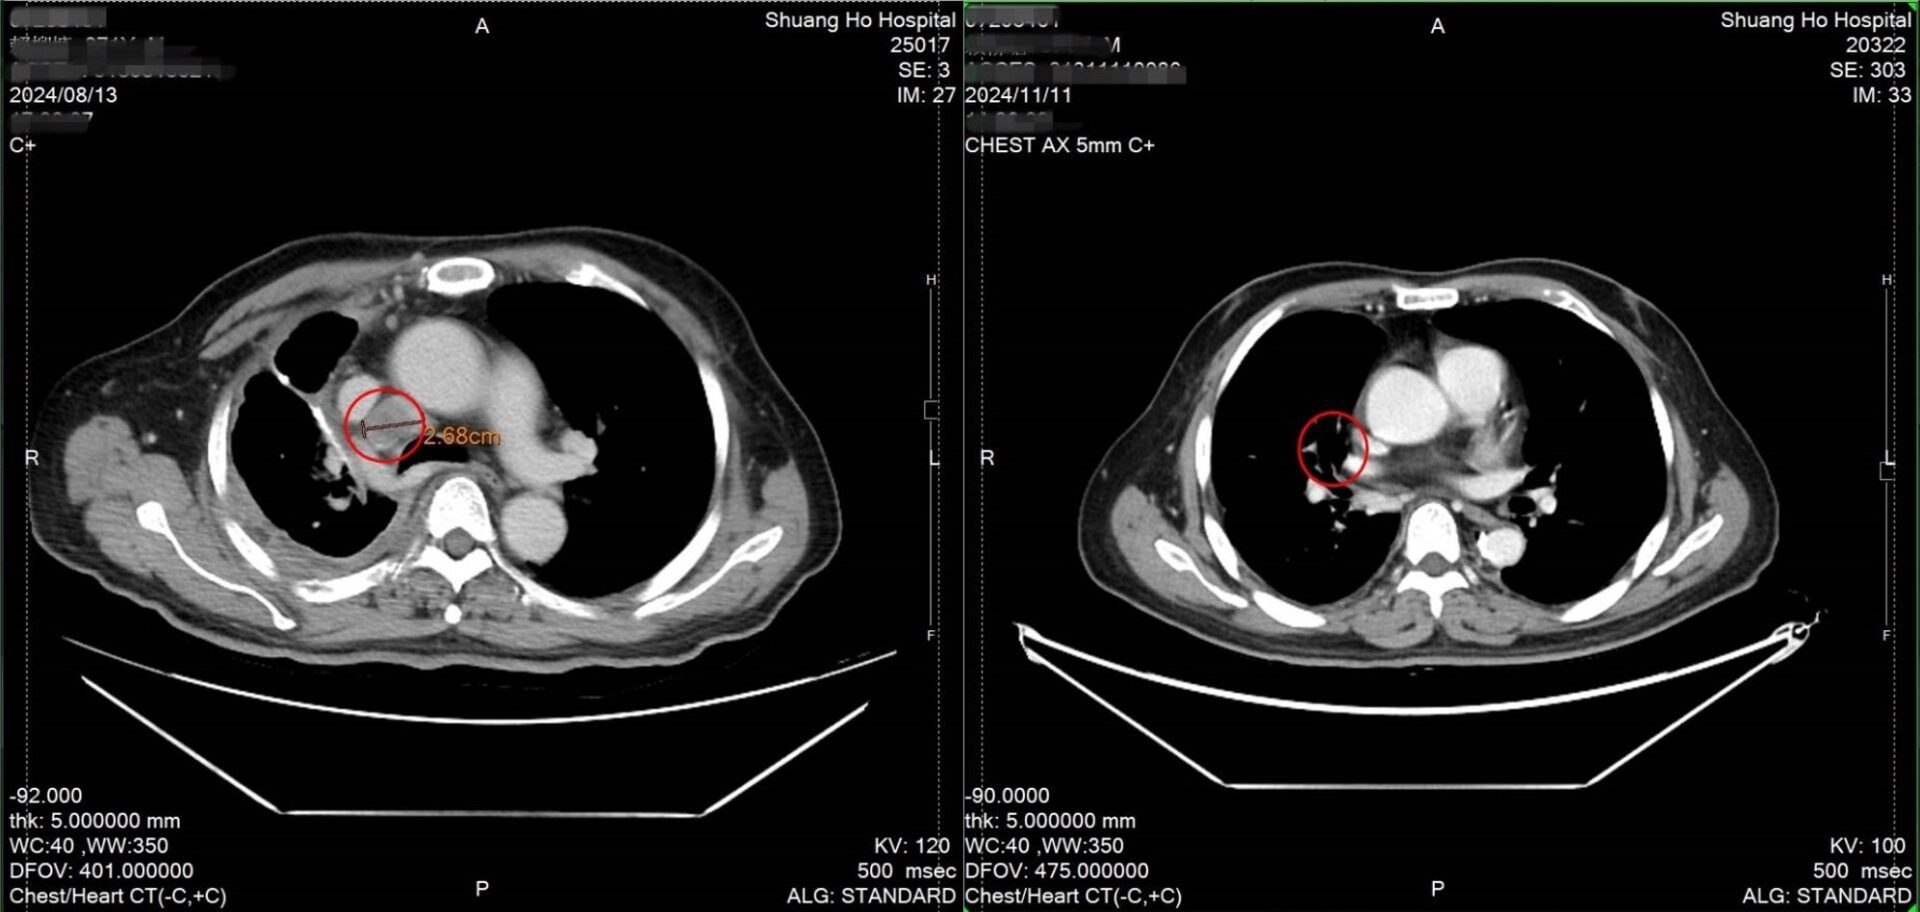

雙和醫院血液腫瘤科主任謝燿宇醫師指出,從治療前的影像檢查中可明顯看到肺部腫瘤持續擴大,除透過基因篩檢找出合適的標靶藥物外,合併搭配每劑間隔兩周,共六劑的DC-CIK細胞回輸治療也是關鍵,後續透過電腦斷層檢查可明顯看到腫瘤縮小,部分腫瘤甚至消失;除療效顯著外,更重要的是幾乎無副作用產生,精神與體力並無影響,未來只需按照醫囑定期回診即可。

↑圖說:經DC-CIK細胞治療治療後檢查發現腫瘤明顯縮小,部分腫瘤甚至消失。(左圖治療前,右圖治療後)(圖片來源:雙和醫院提供)